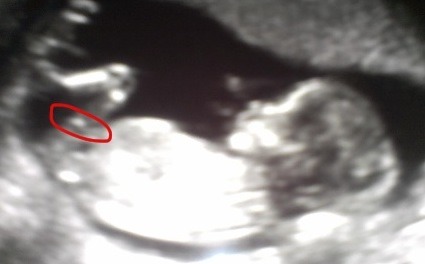

Gender? NUB GUESSES? 13.1 nt scan ultrasound - could it still be a girl